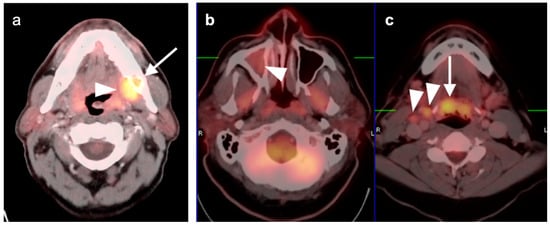

2.2. Squamous Cell Carcinoma of the Head and Neck (SCCHN)

2.3. Nasopharyngeal Carcinoma